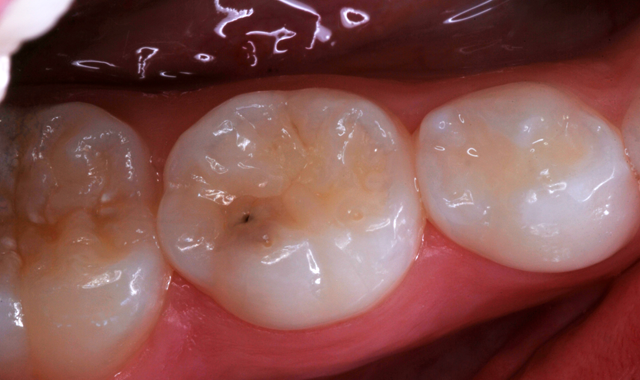

Recently, a mother brought in her 6-year-old daughter who had an occlusal caries lesion of a mandibular primary second molar (Fig. 1). I told the mother about all the advantages of glass ionomer filling materials, and I also related that KetacTM Universal, introduced in September of 2016, was the latest advancement and an excellent choice for her daughter’s treatment.

Fig. 1 Fig. 2